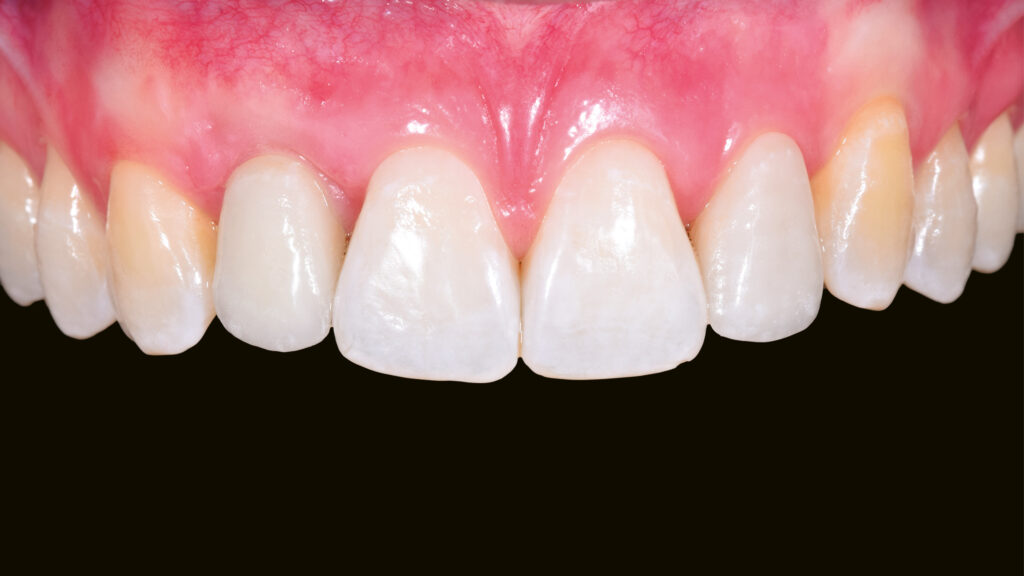

Eingliederung der Implantatkrone

Nach einigen Monaten war das periimplantäre Weichgewebe endgültig stabilisiert. Es zeigte sich noch eine leichte Narbenbildung am Gingivazenit. Nach vorsichtigem Ausdrehen der provisorischen TempShell-Krone offenbart sich eine gut ausgebildete Weichgewebsarchitektur. Die Gewebedicke an der Implantationsstelle ist vergleichbar mit der Situation am zu kopierenden linken lateralen Schneidezahn (Abb. 64). Die Zirkonoxidkrone mit Titanadapter wird definitiv mit dem Implantat verschraubt. Durch die detaillierte digitale Vorbereitung sind oft nur kleine Korrekturen notwendig. Meist können die Restaurationen ohne Einprobe eingegliedert werden. Die biokompatiblen Anteile der Implantatkrone (Titanadapter) und die subgingivalen Anteile der Implantatkrone gewährleisten eine optimale Anlagerung der Gingiva (Abb. 65). Der spaltfreie Sitz der Versorgung auf dem Implantat wird röntgenologisch kontrolliert.

Abschließend kann der Schraubenkanal mit Teflonband und Komposit verschlossen und die statische und dynamische Okklusion überprüft werden. Bei der Eingliederung einer Frontzahnimplantatkrone kommt es vor allem auf eine ästhetische Integration an. Neben der weißen Ästhetik ist die rote Ästhetik mit der Ausformung des Emergenzprofils und der Harmonie des Gingivaverlaufs wichtig. Die Restauration fügt sich ästhetisch gut in die Zahnreihe ein (Abb. 66 bis 68). Das Zusammenspiel der dentalen und gingivalen Umgebung sowie der Lippen mit der prothetischen Versorgung ergibt ein harmonisches Gesamtbild (Abb. 69). Einige Monate nach dem Einsetzen der Implantatkrone hat sich die Gingiva sichtbar gut erholt (Abb. 70).